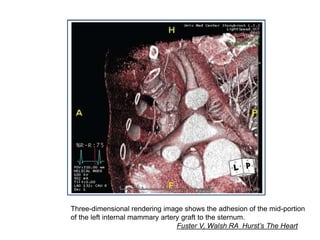

Three-dimensional rendering image shows the adhesion of the mid-portion

of the left internal mammary artery graft to the sternum.

Fuster V, Walsh RA Hurst’s The Heart

Three-dimensional rendering imageshows the adhesion of the mid-portion of the left internal mammary artery graft to the sternum. Fuster V, Walsh RA Hurst’s The Heart